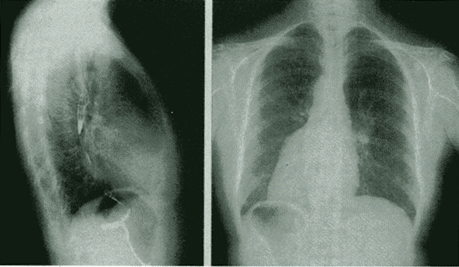

四、风湿性二尖瓣狭窄(左心房增大、右心室增大)

1.左心房增大

(1)心左缘可见左心耳形成的第三弓影(心腰弧形突出)。

(2)左侧位服钡剂示,食管中段受压向后移位。

2.右心室增大

(1)心右缘圆隆。

(2)左心缘下段圆钝。

3.心影呈梨形。